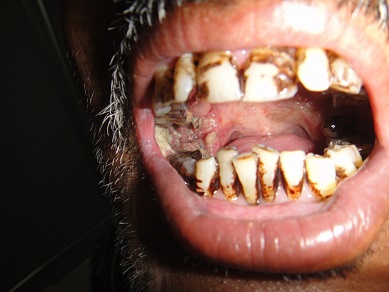

32 YEARS OLD MALE SUFFERING FROM RIGHT LOWER GINGIVO BUCCAL MUCOSA CARCINOMA INVOLVING RIGHT RETROMOLAR TRIGONE.PATIENT HAS ACTIVE PULMONARY TUBERCULOSIS.RIGHT RADICAL NECK DISSECTION WITH RIGHT DISTAL MANDIBULECTOMY WITH RIGHT LOWER ALVEOLECTOMY WITH RIGHT PECTORALIS MAJOR MYOCUTANEOUS FLAPE DONE.